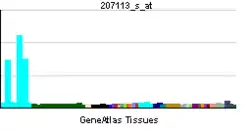

TNF was thought to be produced primarily by macrophages,[52] but it is produced also by a broad variety of cell types including lymphoid cells, mast cells, endothelial cells, cardiac myocytes, adipose tissue, fibroblasts, and neurons.[53] Large amounts of TNF are released in response to lipopolysaccharide, other bacterial products, and interleukin-1 (IL-1). In the skin, mast cells appear to be the predominant source of pre-formed TNF, which can be released upon inflammatory stimulus (e.g., LPS).[54]